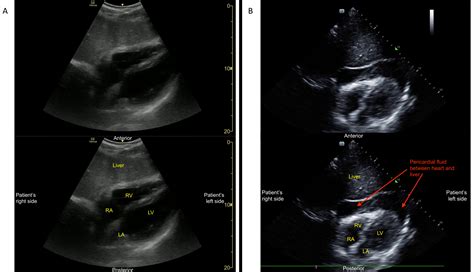

• EFAST (Extended Focused Assessment with Sonography for Trauma): This is a comprehensive ultrasound examination used to evaluate patients with trauma. It includes views of the heart, lungs, abdomen, and pelvis to detect fluid collections, pneumothorax, and other injuries.

• Focused Cardiac Ultrasound: This component evaluates the heart's structure and function, helping to identify conditions such as pericardial effusion, cardiac tamponade, and global cardiac function.

• Trauma Assessment: In trauma patients, the Fast Exam Ultrasound helps identify internal injuries, such as hemoperitoneum, hemothorax, and pericardial effusion.

• Cardiac Evaluation: It is used to assess cardiac function, detect pericardial effusion, and evaluate global cardiac performance.